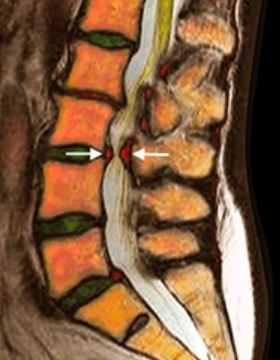

МРТ поясничного отдела позвоночника. Т2-взвешенная сагиттальная МРТ. Стеноз позвоночного канала.

МРТ поясничного отдела позвоночника. Рецидивная грыжа диска. Т2-зависимые МРТ в сагиттальной и аксиальной плоскостях.